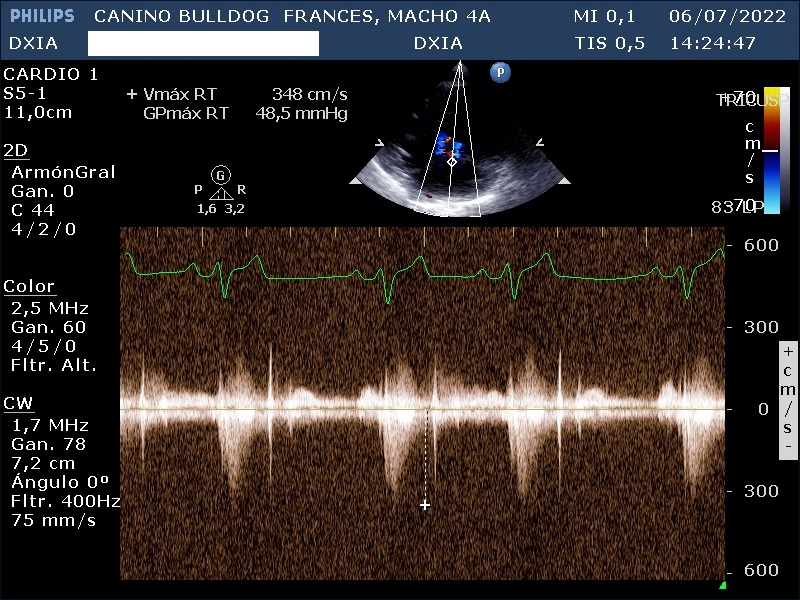

- Válvula tricúspide: Normoimplantada. Valva parietal más alargada que la valva septal. Flujo regurgitante leve-moderado de Vmáx RT: 348 cm/s y GPmáx RT: 48,5 mmHg.

Estudio compatible con la existencia de estenosis pulmonar leve que puede solventarse mediante tratamiento quirúrgico, displasia de la válvula tricúspide con flujo regurgitante moderado y flujo en la válvula mitral sin cambios morfológicos significativos. Además, presenta dilatación de cámaras derechas e izquierdas.